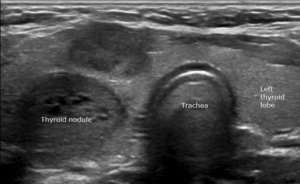

A thyroid nodule refers to an abnormal collection of thyroid cells and tissue, forming a physical lump or growth in the thyroid gland. While most nodules are benign and age-related, it is essential to investigate and rule out cancerous nodules. Read more on thyroid nodules.

Several test may be required when thyroid nodules are detected. These include blood tests and ultrasound examinations of the thyroid gland. Ultrasound helps characterize the nodules and identify any additional ones. Based on size and features, your surgeon will determine if a thyroid biopsy in form of FNAC is necessary.